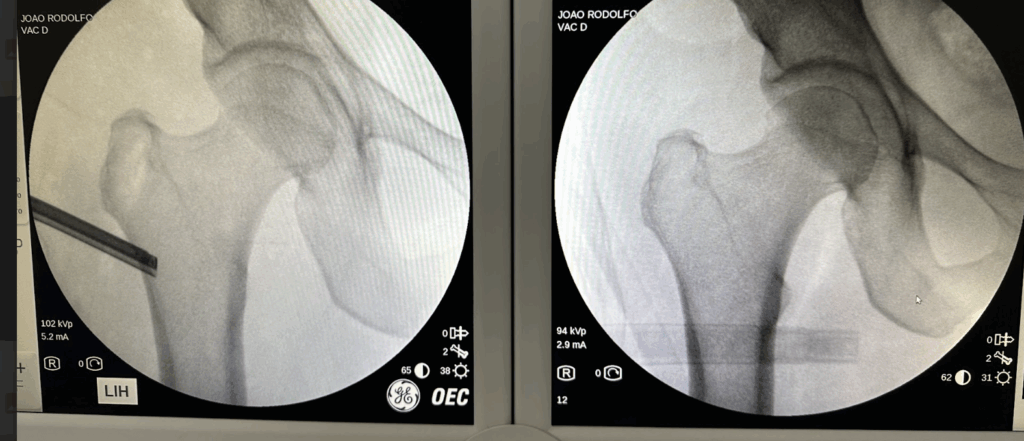

Se os sintomas persistirem mesmo após o tratamento conservador, pode ser necessário um procedimento cirúrgico. A cirurgia é feita por artroscopia (vídeo), com o objetivo de fazer uma raspagem do fêmur ao nível do pequeno trocânter e aumentar o espaço entre os ossos e reduzir a compressão do músculo e do nervo. É uma técnica avançada, realizada por especialistas experientes.

Os maiores riscos da cirurgia são: lesão do nervo ciático e lesão da artéria que nutre a cabeça do fêmur ocasionando osteonecrose da cabeça femoral.